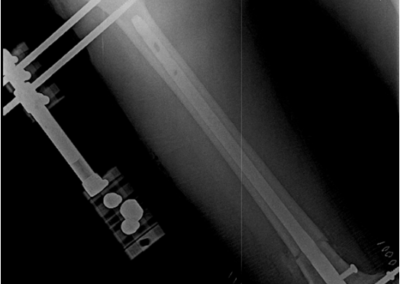

Lengthening SurgeryDec 30, 2021 | Case Examples Case 1: Tibiada Extension Over Nail (LON) Case 2: Femurda Extension Over Nail (LON Case 3: Femurda Automatic Nail Extension